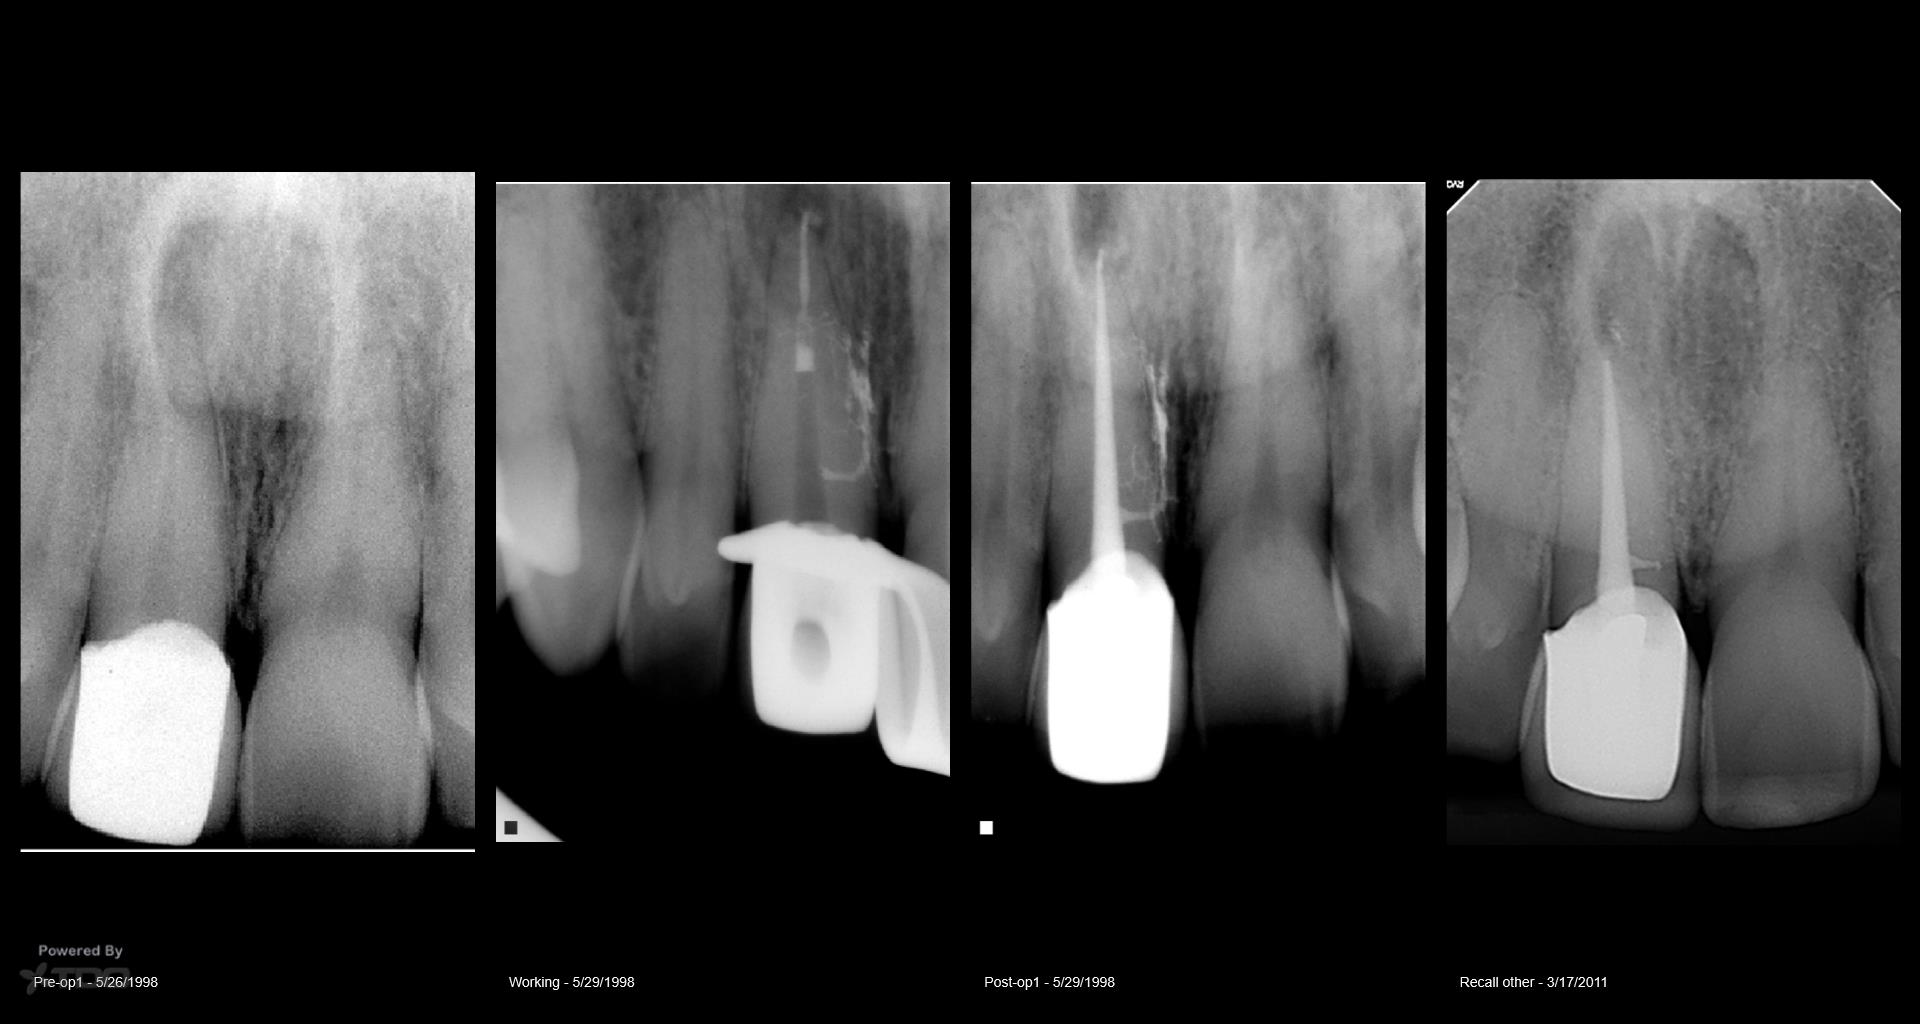

20 yr recall today

Don you just love anterior teeth recalls?